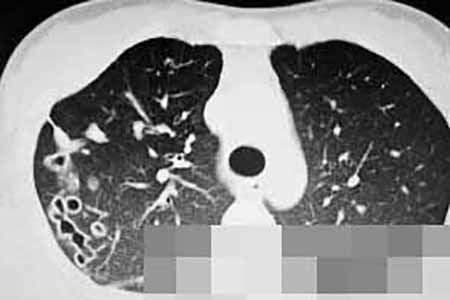

女子肺里长满虫 咳血三年只因爱吃这【必看】

女子肺里长满虫 咳血三年只因爱吃这,年仅23岁的云南姑娘小夏咳血三年,被当成是结核病治疗三年无效,近日CT发现,小夏的肺里全都是虫游动的痕迹......